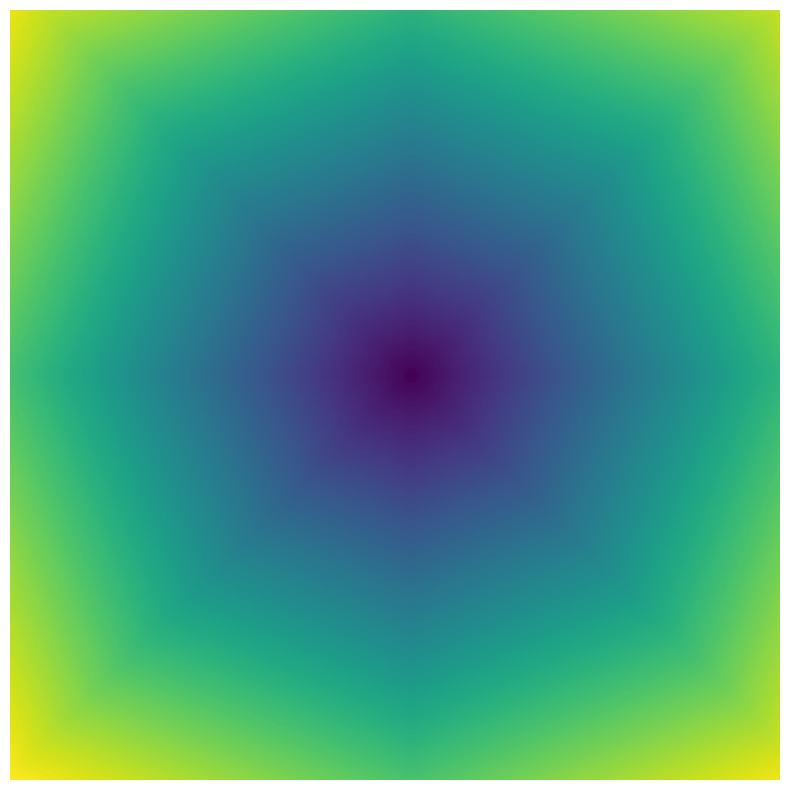

Generally, given an exact, full annotation of an object, such a Euclidean signed distance map encodes also information on the shape of an object. But when using a weak ground truth , where and , inferring a correct extent and shape of the objects is nontrivial. As shown in 1(b), Euclidean distance calculated from a point label source grows radially, regardless of the actual shape of the object, and thus makes little sense from an information point of view. Under the assumption of intra-object homogeneity and inter-object contrast (w.r.t intensities), this problem can be circumvented to a degree by using a distance function that takes also intensity values into account. An example of a commonly used distance measure with an intensity component is the Geodesic distance ([34]). Let denote a path between , with and being neighbors under a chosen adjacency relation. Reusing the notation from before, a Geodesic distance map from the boundary of the ground truth class , , can be defined as

Both the Intensity and the Minimum barrier distance are defined exclusively on the image intensity space. However, from the examples of distance map in 1(d), we can notice that the values still increase somewhat radially from the annotation. This behaviour is similar to the one of the Geodesic distance in 1(c) (which actually includes the spatial proximity in its definition), and is due to the summing operator in the general Geodesic distance definition in Equation 3. While the intensities of two neighboring pixels on a path may be the same, that will rarely be the case in real life, noise riddled images. This makes the Intensity distance function approximately monotonically increasing with increasing length of the path (in space), even on paths where the intensity is mildly fluctuating (e.g. consider a path with even pixels intensity value of and odd pixels intensity value of ). One could thus argue that such a definition of a distance, despite being based exclusively on intensities, is still capable of loosely encoding the spatial distance information.

On the other hand, while we can see that the MBD based maps are similar to Geodesic and Intensity ones (1(e)) with respect to the object shape recovery, they have a less pronounced and smooth increase in the values outward from the source point.

In contrast to Euclidean distance, the Geodesic, Intensity and Minimum barrier distance maps all encode contrast sensitivity and preserve the object structures by harnessing the intensity information of the underlying image. This holds even when calculated from point sources. In practice, using such maps for network training could mean a lower penalty for false positives that occur farther from the point annotation but are close to it in intensity. Thus still enabling the propagation of a sort of shape information (as it can be inferred from the raw image intensities).